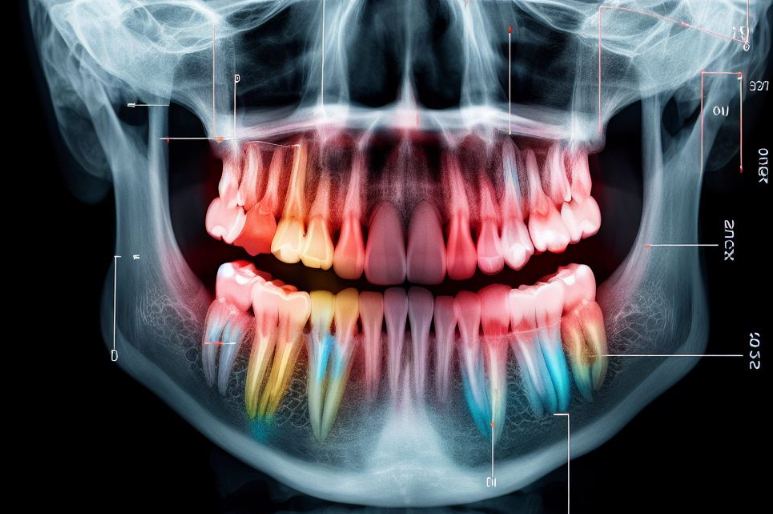

사랑니에도 때로는 치아 추출을 고려해야합니다.

보통 17~18세쯤 되면 총 4개의 사랑니(상, 하, 좌, 우)가 나기 시작합니다. 그 양은 사람마다 다를 수 있지만 전혀 존재하지 않거나 외부에 노출되지 않는 경우도 있습니다. 사랑니는 치과에서는 "제3대구치"라고 부르며 입의 가장 안쪽에 자라는 제3대구치입니다. '막니'라고도 불리며, 서양에서는 지혜가 자라는 나이에 태어난다고 하여 '사랑니'라고도 합니다. 대다수의 사람들은 사랑니가 존재한다는 팩트를 모르고 있지만, 치과 검진을 통하여 발견되는 경우가 많습니다.

사랑니를 가지런히 하면 문제가 없지만, 입의 구조상 치아의 끝에 위치하여 관리가 어려워 충치, 잇몸질환, 구취 등의 이유가 됩니다. 사랑니는 다른 치아에 비해 늦게 나오기 때문에 곧게 자라지 못하고 가끔은 옆으로 누워 있거나 잇몸 아래에 매복되어 잇몸질환이 발생하여 잇몸이 부어 오르거나 턱뼈에 낭종이 생기기도 합니다.

우리나라 국민의 60~80%는 사랑니를 발치하게 되지만, 사랑니가 잇몸 속에 자리잡고 있어 기울어지거나 일부만 발치되는 등 통제할 수 없이 발치되는 경우도 많습니다. 그러니까 이빨이 제2대구치와 접촉되어 있거나 턱 깊숙한 곳에 자리한 경우 이빨을 발치해야 합니다. 또한, 잇몸 끝이 가렵고, 양치할 때 때때로 피가 나고, 혀가 부어오르고, 손으로 만지기 힘들고 고통이 있는 경우라면 치과 전문가들은 이빨을 발치하는 것을 권합니다.

통증이나 증상이 없더라도 맹출되는 사랑니는 다른 치아와 크기가 다를 수도 있고, 성장률 방향이나 과정에서 따라 주변 치아에 영향을 미칠 수도 있습니다. 충치나 감염이 사랑니 앞의 어금니에 영향을 주어 손상시킬 수 있을 뿐만 아니라 발치 자체도 어려울 수 있습니다.